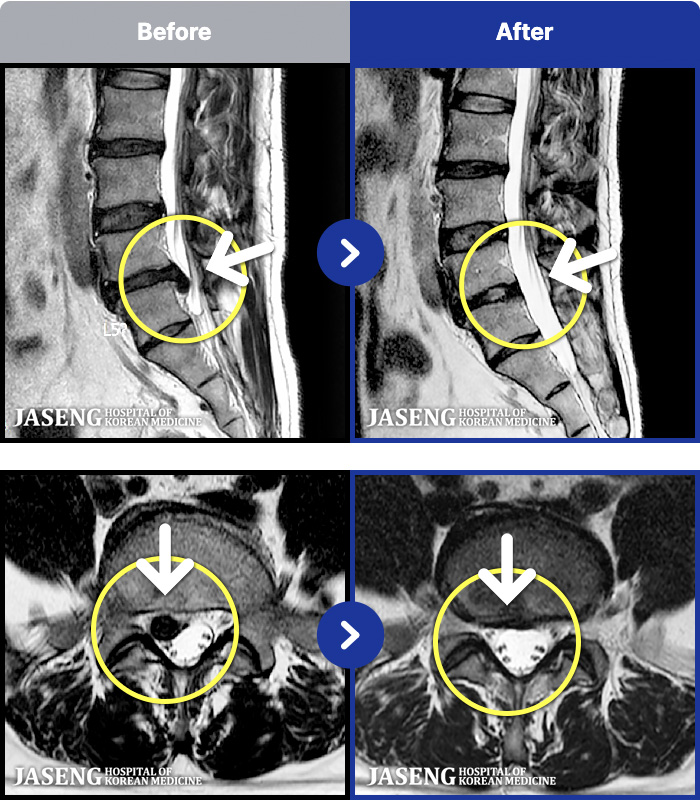

- MRI ġ

MRI ġ

191 MRI ũ ʸ Ȯϼ.